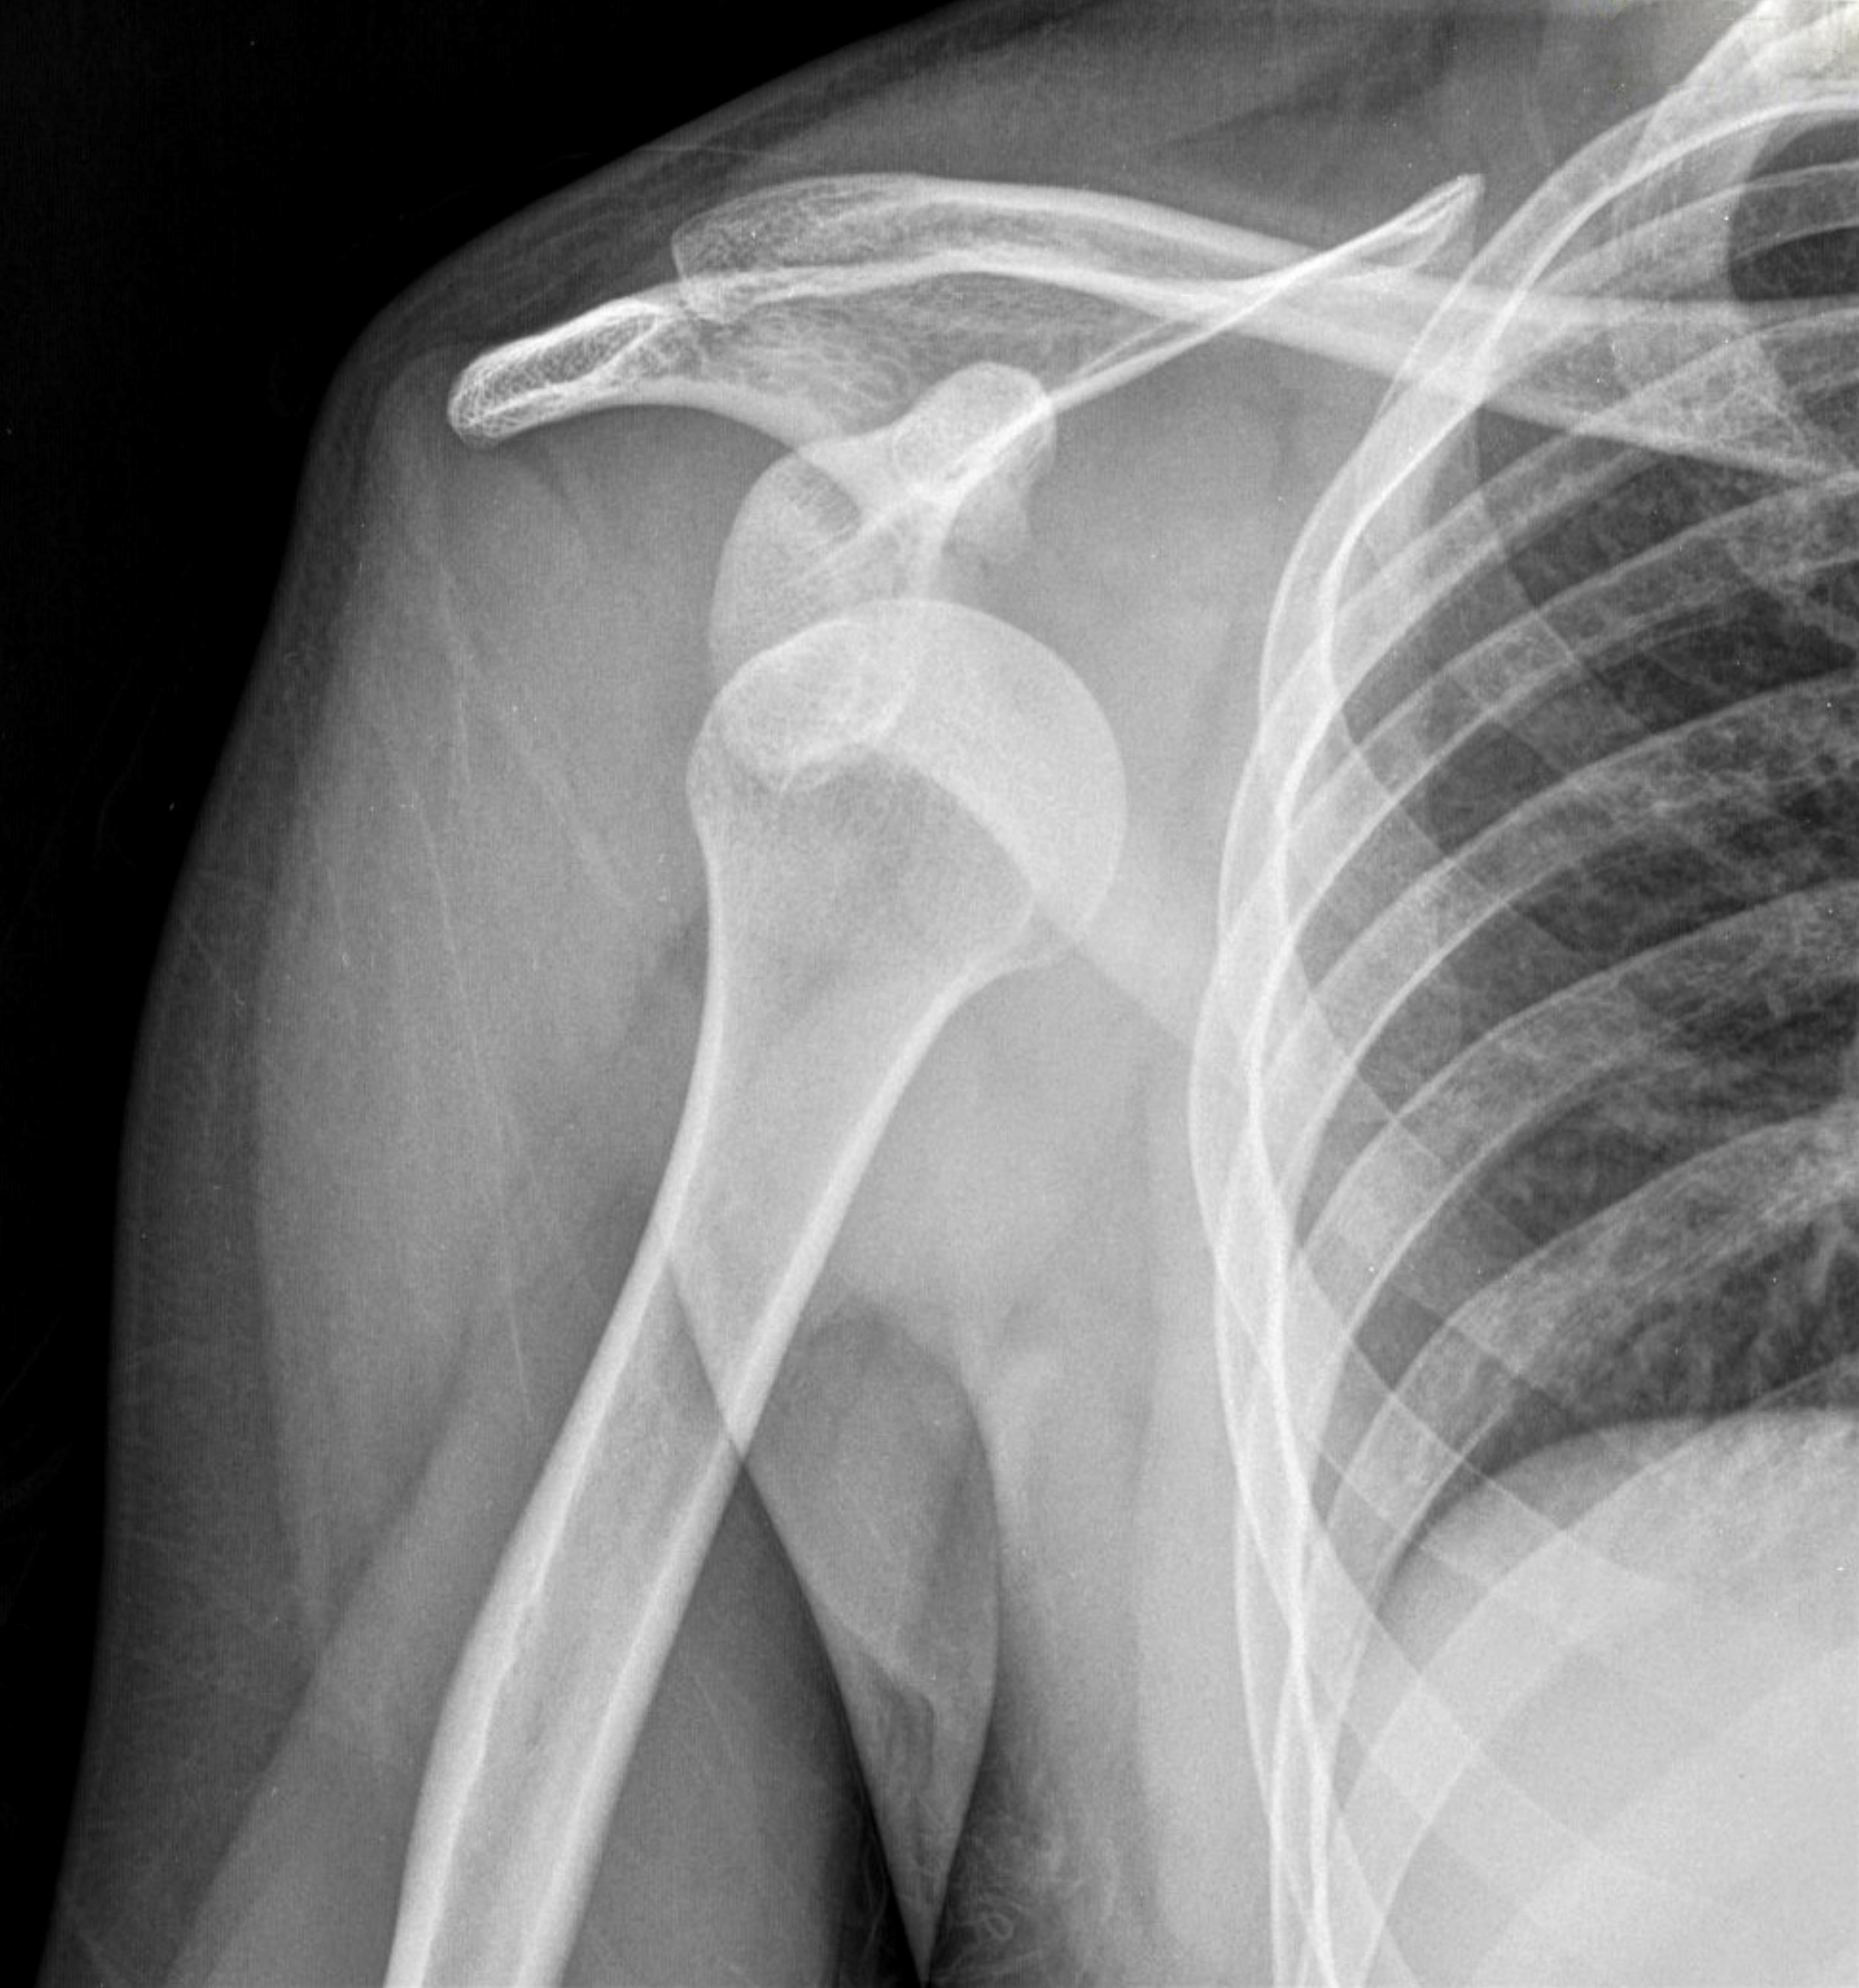

습관성탈구

어깨가 한번 빠지고 난 후 구조물이 손상돼 가벼운 충격에도 반복적으로 어깨가 빠지거나 빠질 것 같은 불안정성이 발생하는 질환입니다.

주요 원인과 증상

원인

· 어깨인대가 선천적으로 약한 경우

· 관절낭이 많이 늘어나 있는 경우

· 과거 어깨탈구 발생 후 치료를 소홀히 한 경우

· 어깨사용이 많은 직업이나 운동을 좋아하는 젋은층

증상

· 초기 어깨 탈구 시 심한 통증

· 횟수가 잦아지면서 통증은 줄어드나 쉽게 탈구 됨

· 탈구의 방향에 따라 특정 위치로 고정되어 움직일 수 없음

· 어깨의 삼각근 부위가 편평해지거나 오목하게 들어감

· 심한 경우 감각이상 및 운동장애 발생발생

치료

보존적 치료

어깨관절의 적절한 휴식과 함게 체외충격파치료 또는 물리치료 및 주사치료, 약물치료 등의 비수술적 치료를 시행합니다.

수술적 치료

관절내시경 기구를 이용하여 찢어진 관절와순을 봉합합니다.